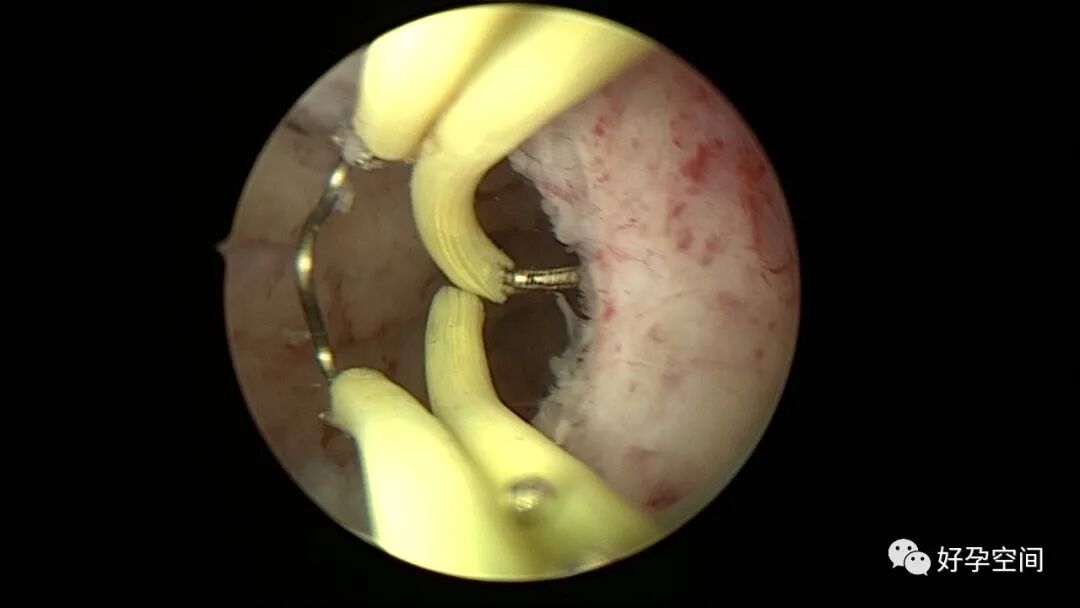

病例2:患者31岁,原发不孕,2019年11月在重庆某妇幼保健院做宫腹腔镜手术疏通输卵管,术中未取内膜活检,术后未孕。2021年7月在成都某大型生殖中心试管怀孕双胎(移植前未做宫腔镜检查及内膜活检),2021年11月孕4月双胎破水,在达州当地医院引产清宫,清宫术后40天复诊B超提示宫腔胚物残留。2022年1月到我院(眉山蕴缨妇产医院)行宫腔镜手术切除残留组织,2022年4月宫腔镜术后3个月复诊B超提示宫腔粘连,再次来我院行宫腔镜分粘。宫腔被覆一层沙丘状质脆增生组织,宫腔下段两侧壁内聚,行分粘术,取内膜送病检。

子宫内膜结核是由结核分枝杆菌在子宫内膜部位种植引起的炎症,是仅次于输卵管结核的常见女性生殖器结核。子宫内膜结核常由输卵管结核蔓延而来,多继发于盆腔腹膜结核或肺结核。子宫内膜结核的超声表现主要为:子宫内膜回声不均匀、宫腔内结节样病灶、宫腔内强回声灶、单纯的子宫内膜薄等。盆腹腔超声显示输卵管炎性表现:输卵管增粗、肥厚、扭曲、僵硬、输卵管积液积脓、卵巢旁混合性包块、输卵管系膜囊肿、盆腔包裹性积液等。术中所见:盆腹腔组织粘连、盆腹腔粟粒样结节、结核球、脓肿等,输卵管伞端烟斗样外翻,输卵管内充满淡黄色干酪样或豆渣样组织。宫腔镜显示宫腔狭窄、宫壁僵硬、宫内膜肉芽肿样增生、内膜质脆易刮除、干酪样组织、脓液等。

温宝宁等将子宫内膜结核宫腔镜检查的镜下表现分为:①宫腔形态、大小正常,双侧输卵管开口可见,子宫内膜发红、增厚,局部突起,表面可见少量质脆的小颗粒状赘生物,可刮出质脆的子宫内膜组织;②宫腔形态正常,但是宫腔内无正常子宫内膜,均被覆一层苍白的绒毛状或棉絮状质脆组织,血管少,无异形血管,宫腔内病灶与正常组织分界明显;③宫腔形态异常,呈窄桶状,子宫内膜瘢痕化,输卵管开口细小,甚至宫角消失。